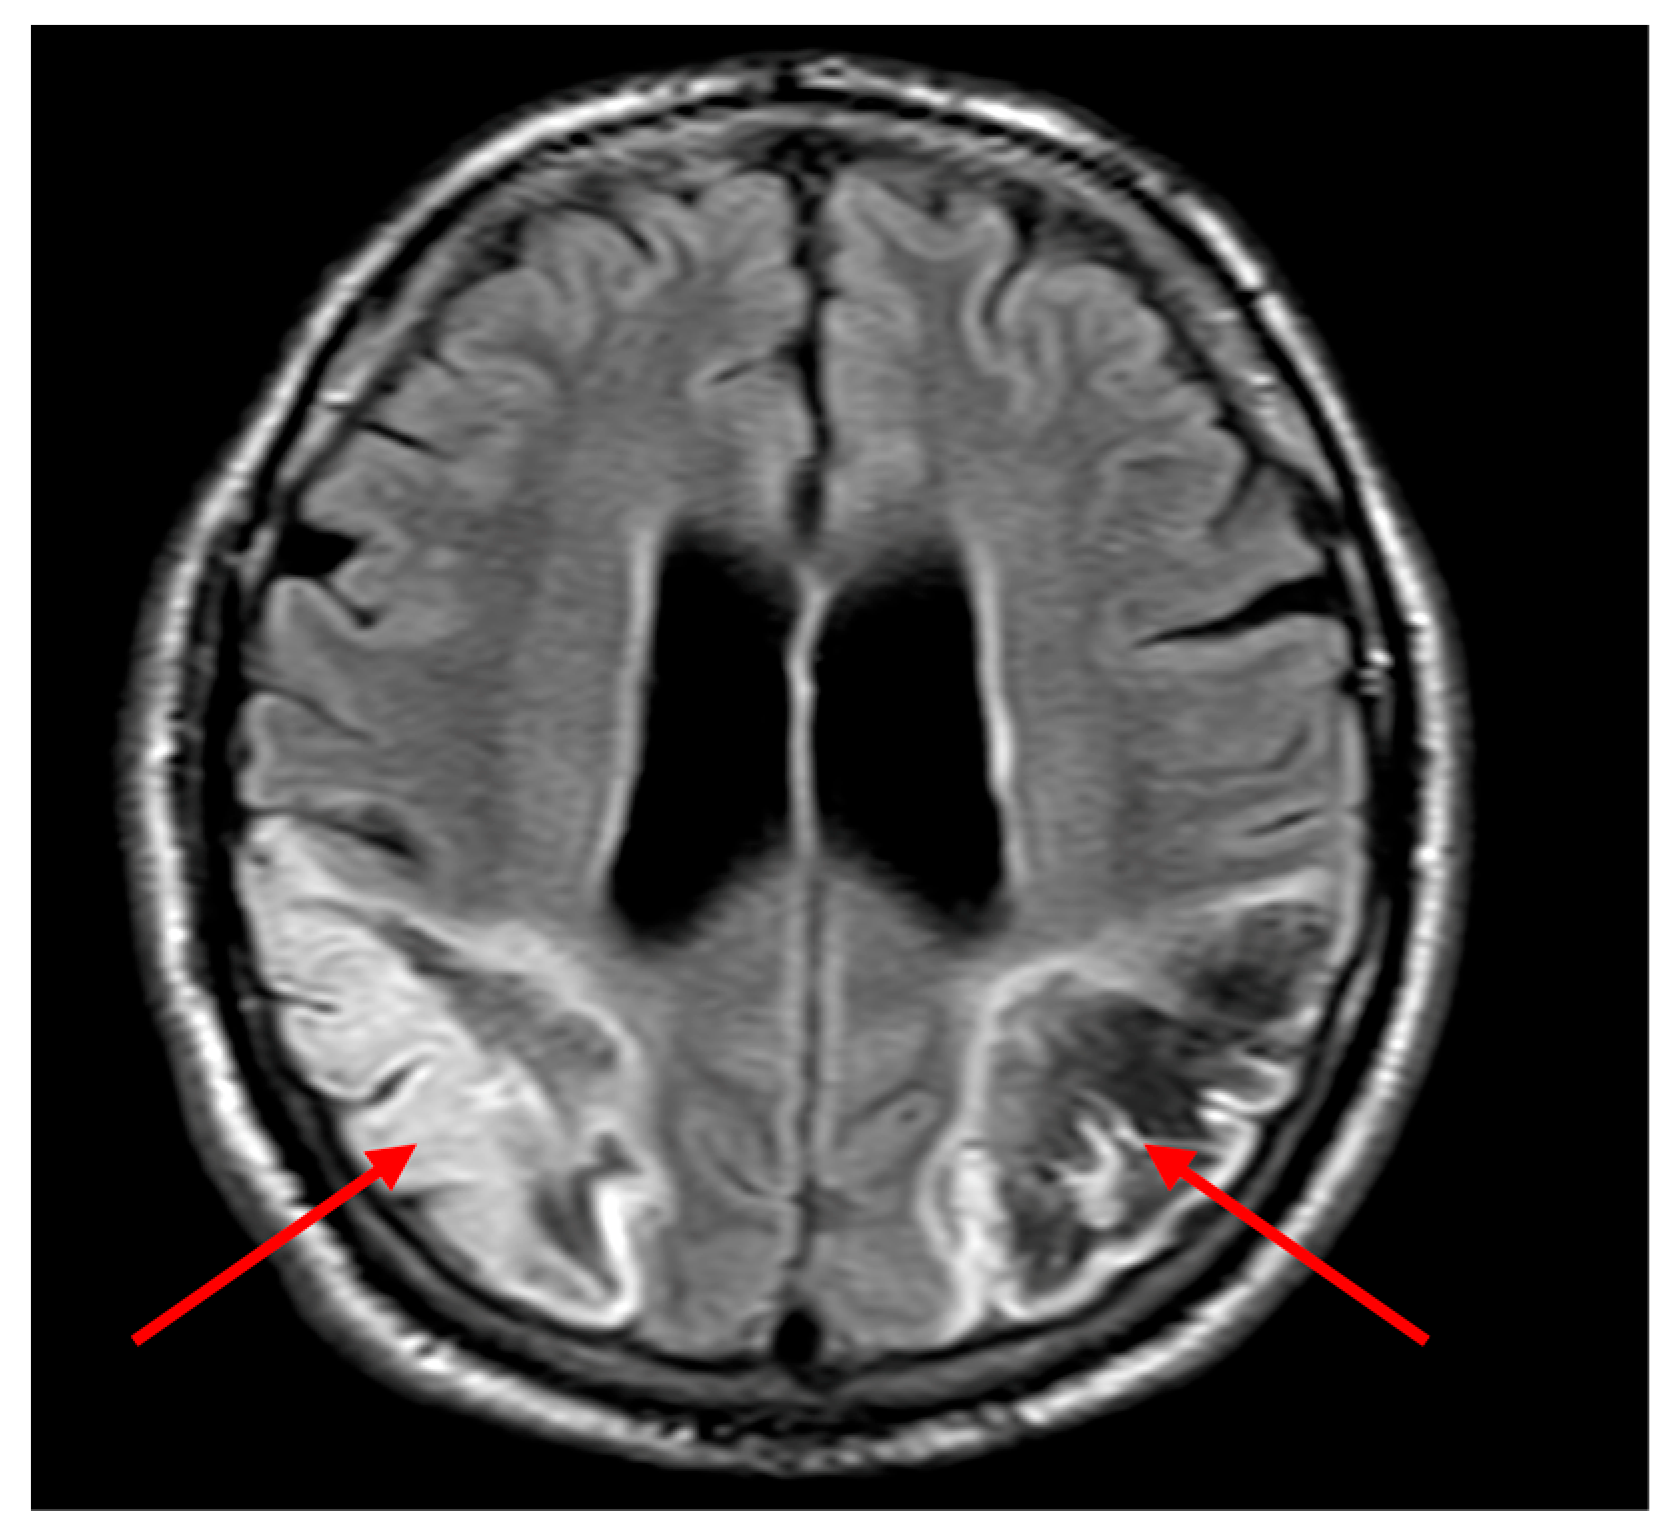

On day 2, further neurological signs evolved including cortical visual loss, persistent dysphasia, and neurocognitive impairment. By day 3, the patient demonstrated visual inattention, inability to follow two-step commands, and absent visual threat on the left. Diffusion-weighted MRI revealed a large acute infarct in the left parietal lobe and a subacute infarct in the right parietal region (Figure 2a). Fast field echo sequences indicated haemorrhagic transformation of the left-sided infarct (Figure 2b). Aspirin was discontinued, with plans for repeat imaging to guide anticoagulation restart.

Clinically, the patient presented with an atypical and rapidly evolving neurological syndrome. Initial confusion and agitation, coupled with impaired command following, likely delayed recognition of the cerebrovascular insult. Neuroimaging subsequently revealed bilateral parieto-occipital infarctions, accounting for the constellation of cognitive, sensory, and visual disturbances observed. Imaging revealed infarcts predominantly involving the left angular gyrus (Brodmann area 39) and adjacent inferior parietal lobule, regions classically associated with Gerstmann syndrome. The right parieto-occipital lesion affected the non-dominant hemisphere’s homologous areas, contributing to spatial neglect and impaired visual awareness. On diffusion-weighted MRI (Figure 2a), the infarcted regions aligned with cortical areas subserving symbolic representation and spatial mapping. Notably, the haemorrhagic transformation (Figure 2b) likely limited early re-initiation of anticoagulation, underscoring the clinical utility of sequential imaging. These anatomical correlates correspond well to the observed deficits and support a network-based model of cognitive disruption.

Figure 2. Bilateral Parietal infarcts on MRI (a) Diffusion weighted imaging (DWI) shows a large acute cortical infarct in the left parietal lobe (yellow arrow), with a subacute infarct in the right parietal lobe (red arrow), correlating with the patients cognitive and visuospatial deficits. (b) Fast field echo (FFE) sequence demonstrates haemorrhagic transformation within the left parietal infarct (blue arrow), which informed temporary anticoagulation management.